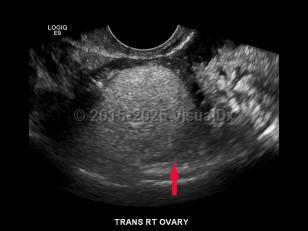

Ovarian cysts

Ovarian cysts are most commonly asymptomatic and diagnosed incidentally on physical exam or imaging. Sometimes the patient with an ovarian cyst may present with acute or chronic abdominal pain.

Depending on the underlying etiology, an ovarian cyst might develop slowly or rapidly. Rapidly forming cysts may be more likely to cause pain. Ovarian cysts, especially functional or physiologic cysts, often resolve spontaneously.